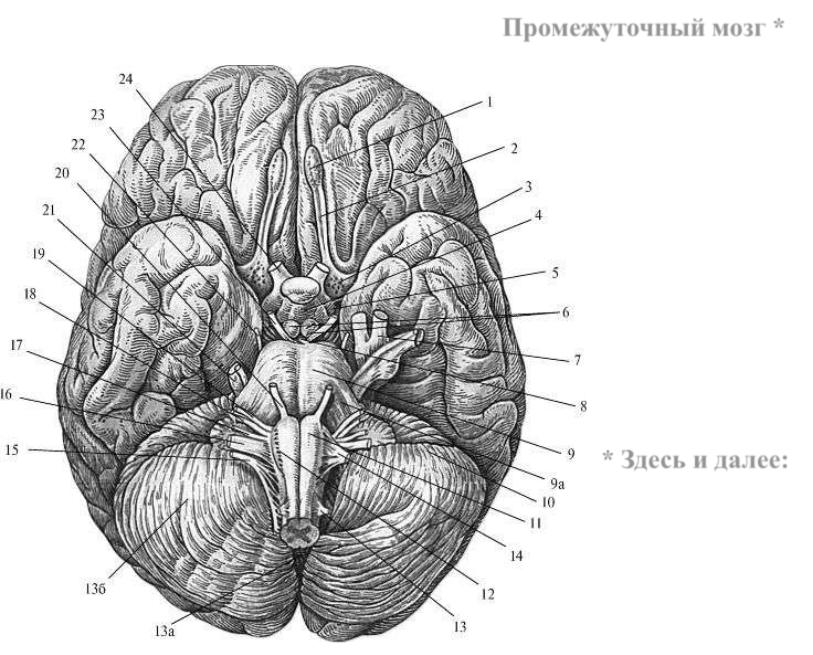

Необычные объекты: Переднее продырявленное вещество